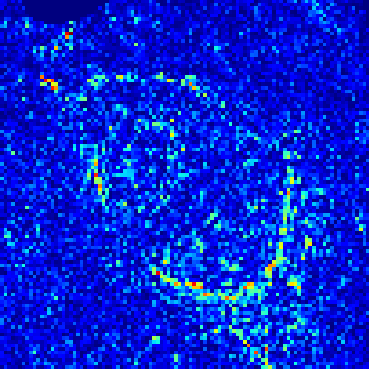

Supervised Deep-Learning (DL)-based reconstruction algorithms have shown state-of-the-art results for highly-undersampled dynamic Magnetic Resonance Imaging (MRI) reconstruction. However, the requirement of excessive high-quality ground-truth data hinders their applications due to the generalization problem. Recently, Implicit Neural Representation (INR) has appeared as a powerful DL-based tool for solving the inverse problem by characterizing the attributes of a signal as a continuous function of corresponding coordinates in an unsupervised manner. In this work, we proposed an INR-based method to improve dynamic MRI reconstruction from highly undersampled k-space data, which only takes spatiotemporal coordinates as inputs. Specifically, the proposed INR represents the dynamic MRI images as an implicit function and encodes them into neural networks. The weights of the network are learned from sparsely-acquired (k, t)-space data itself only, without external training datasets or prior images. Benefiting from the strong implicit continuity regularization of INR together with explicit regularization for low-rankness and sparsity, our proposed method outperforms the compared scan-specific methods at various acceleration factors. E.g., experiments on retrospective cardiac cine datasets show an improvement of 5.5 ~ 7.1 dB in PSNR for extremely high accelerations (up to 41.6-fold). The high-quality and inner continuity of the images provided by INR has great potential to further improve the spatiotemporal resolution of dynamic MRI, without the need of any training data.

翻译:在这项工作中,我们建议了一种基于IRI的方法,用这种方法来改进动态磁共振感应成像(MRI)重建,而该方法只是以高度低劣的 k-空间数据为基础,而该数据仅以磁共振坐标作为投入。具体地说,拟议的IRI将动态MRI图像作为一种隐含功能来表示,并将其编码到神经网络中。网络的权重仅从稀有的(k, t)空间数据本身中学习,而没有外部培训数据集或先前的图像。 利用基于IRI的强有力隐含性稳定化,同时不以清晰的动态和时空坐标坐标坐标坐标坐标作为投入。 拟议的IRIR将动态MRI图像作为一种隐含功能,将其编码到神经网络中。网络的权重仅从淡化的(k, t)空间数据本身学习,而没有外部培训数据集或先前的图像。